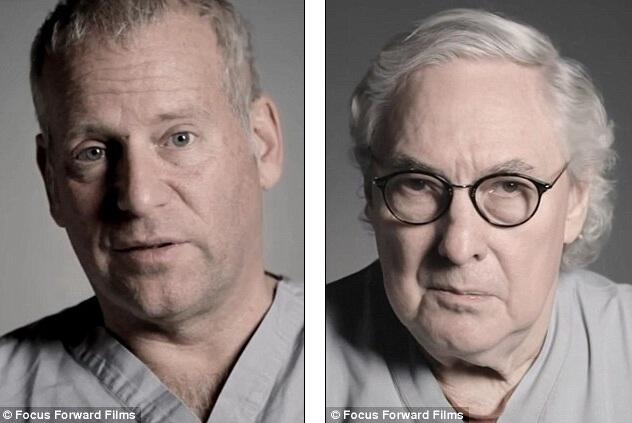

Dr Billy Cohn dan Dr Bud Frazier kemudian menginstal perangkat tersebut setelah mengeluarkan jantung Lewis. Dan dalam waktu beberapa hari, sang pasien sudah bangun dan berbicara dengan dokter.

Kedua dokter tersebut beberapa waktu sebelumnya telah menguji alat ini pada hampir 50 anak sapi. Dimana mereka mengeluarkan hati binatang tersebut, dan pada hari berikutnya sapi-sapi itu berlaku normal seperti makan, tidur, dan bergerak. Namun kali ini, tanpa jantung yang memompa darah ke tubuh mereka. Jika anda mendengarkan dada (sapi) dengan stetoskop, maka anda tidak akan mendengar detak jantung," kata Dr Cohn kepada NPR Juni 2011 lalu.